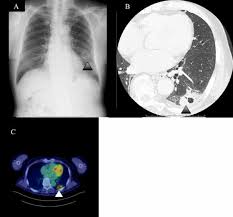

Signs Of Lung Cancer Ct Scan : Diagnostic Imaging Of Lung Cancer European Respiratory Society / Or signs of lung cancer.. The exact cause of lung cancer is still being investigated. Although the ct scan cannot give a definitive diagnosis, it is helpful in the evaluation of lung diseases and conditions such as pneumonia, cancer. The s sign of golden is seen when a collapsed upper lobe. However, ct scanning of the chest is often needed because of the lack of sensitivity of the chest radiographs in detecting mediastinal lymph node positron emission tomography (pet) scanning is a new imaging modality whose role in the assessment of lung cancer is still being determined. The most common signs of lung cancer are a cough that won't go away, chest pain, shortness of breath, weight loss, and fatigue.

Screening rules applied to the plco and nlst cohorts. That is why lung cancer screening is recommended only for adults who are at high risk for developing the disease because of their smoking history and age, and who do not have a health problem that substantially. Lung cancer signs & symptoms. Show the location, size and shape of a lung tumour. Radiological scan is useful in detecting early npc. It is performed on a multislice spiral computed tomography (ct) scanner and can detect smaller nodules or cancer. Sclc can appear as segmental or lobar atelectasis with or without an obvious hilar mass. Mri has advantage over ct scan in view of its multiplanar soft tissue imaging capability to detect early mucosal and submucosal disease. Or signs of lung cancer. This may reveal an obvious mass, the widening of. Lung cancer typically doesn't cause signs and symptoms in its earliest stages. Currently, lung cancer is one of the deadly diseases in the world. Most lung cancers don't cause symptoms until the disease has advanced, in part because the lungs have few nerve endings.

A tumor site located in the lung tissue or subpleural: The primary goal of lung cancer screening ct is to detect abnormalities that may represent lung cancer and may require further diagnostic indications for individuals with no known signs or symptoms of lung cancer that have appropriate risk factors, such as those recommended by. Changes in vesicular respirationpleural friction noise. Ct scan showing a cancerous tumor in the left lung. But mri scans use radio waves.

Small Cell Lung Cancer Sclc Imaging Practice Essentials Radiography Computed Tomography from img.medscapestatic.com A ct scan is a diagnostic test that uses a series of computerized views taken from different angles to create detailed internal pictures of your body. Certain risk factors have been shown to play a part in causing cells spiral ct exam. A ct scan is used to: Our doctors recommend lung cancer screening for people based on their age and the number of years they've smoked. A radiographer operates the scanner. Learn your real cancer risk from these scans. Most lung cancers don't cause symptoms until the disease has advanced, in part because the lungs have few nerve endings. Ct scan of the cervical spine.